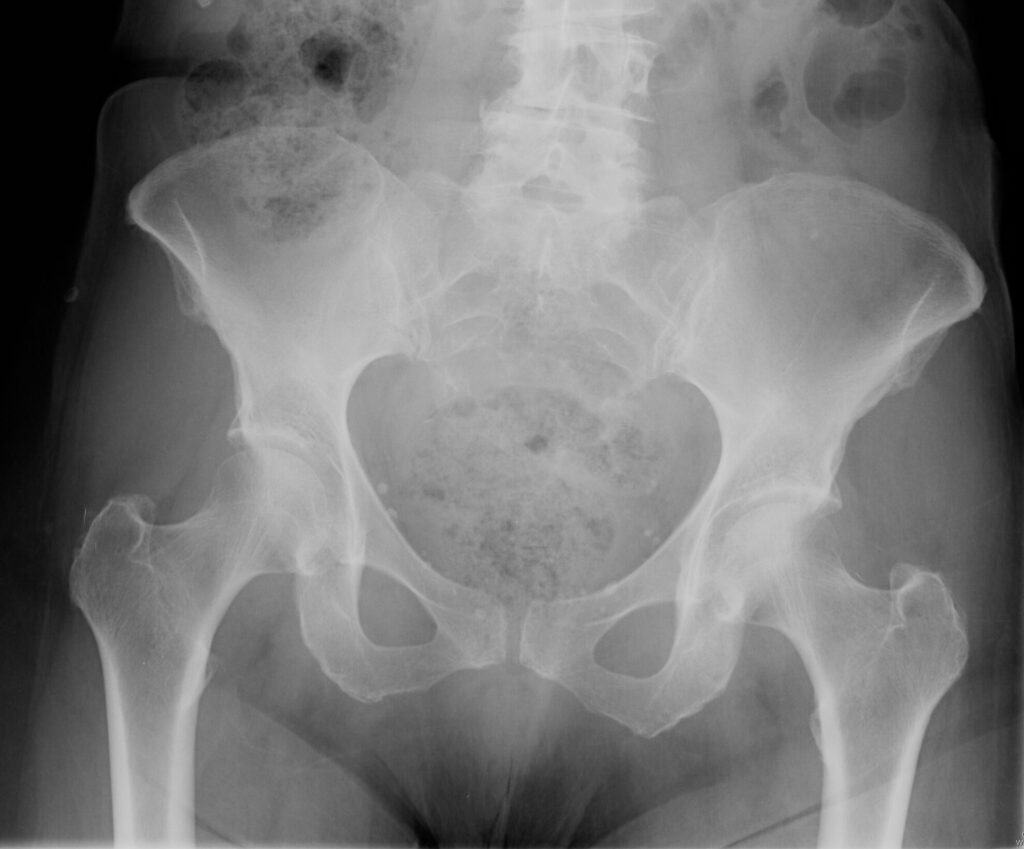

Plain x-ray (Fig. 1-3)

• Midline bone lytic lesion with focus in the vertebral body

• Surrounding soft tissue mass

• Invade intervertebral discs and contiguous vertebras.

Fig. 1-3: Plain X-ray of the sacrum demonstrates a chordoma. There is a lytic lesion of the sacrum with total destruction of the sacrum.